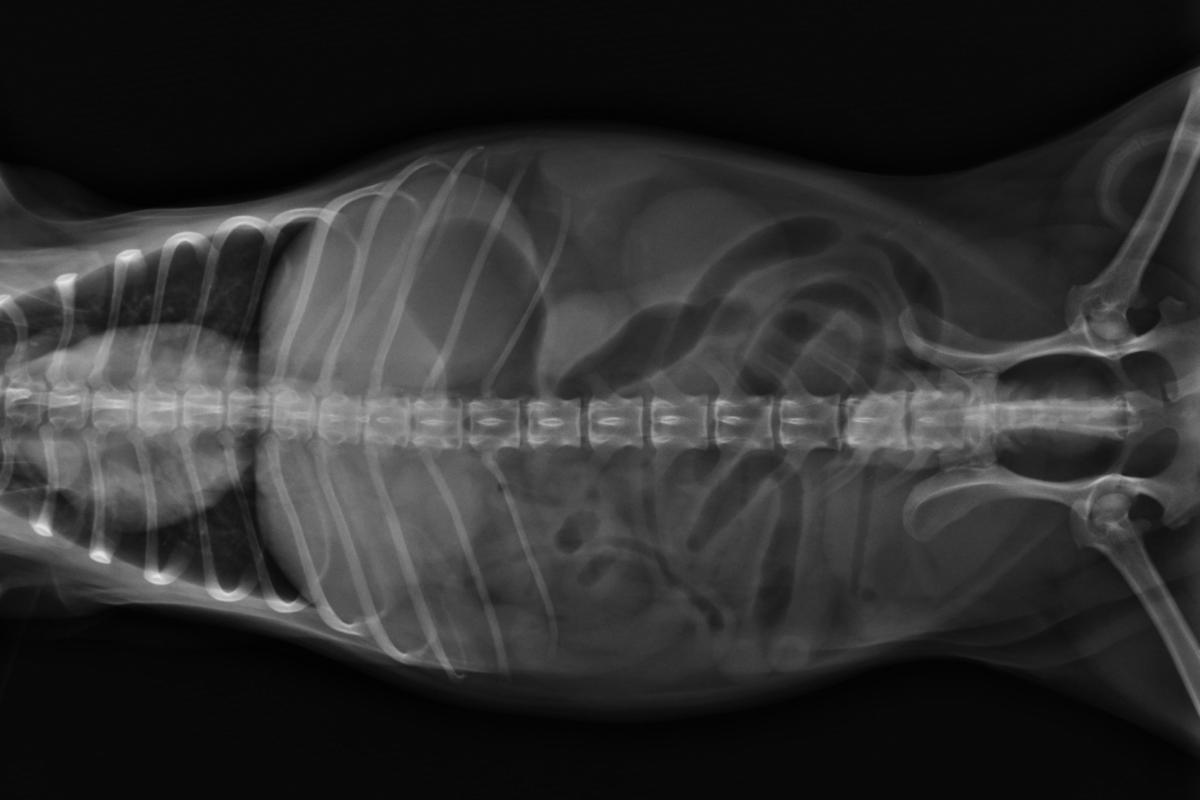

No entanto, o veterinário não pode diagnosticar definitivamente a presença de uma inflamação intestinal sem realizar algum exame complementar que a confirme. Para isso, o mais comum é recorrer a uma análise coprológica, ou seja, um exame das fezes, seu conteúdo e consistência, além de realizar alguma técnica de diagnóstico por imagem que permita observar a aparência do trato digestivo. Nesse sentido, o mais utilizado é a ultrassonografia abdominal, pois é uma técnica pouco invasiva, totalmente inofensiva para o animal e que fornece muitas informações sobre seu estado intestinal.